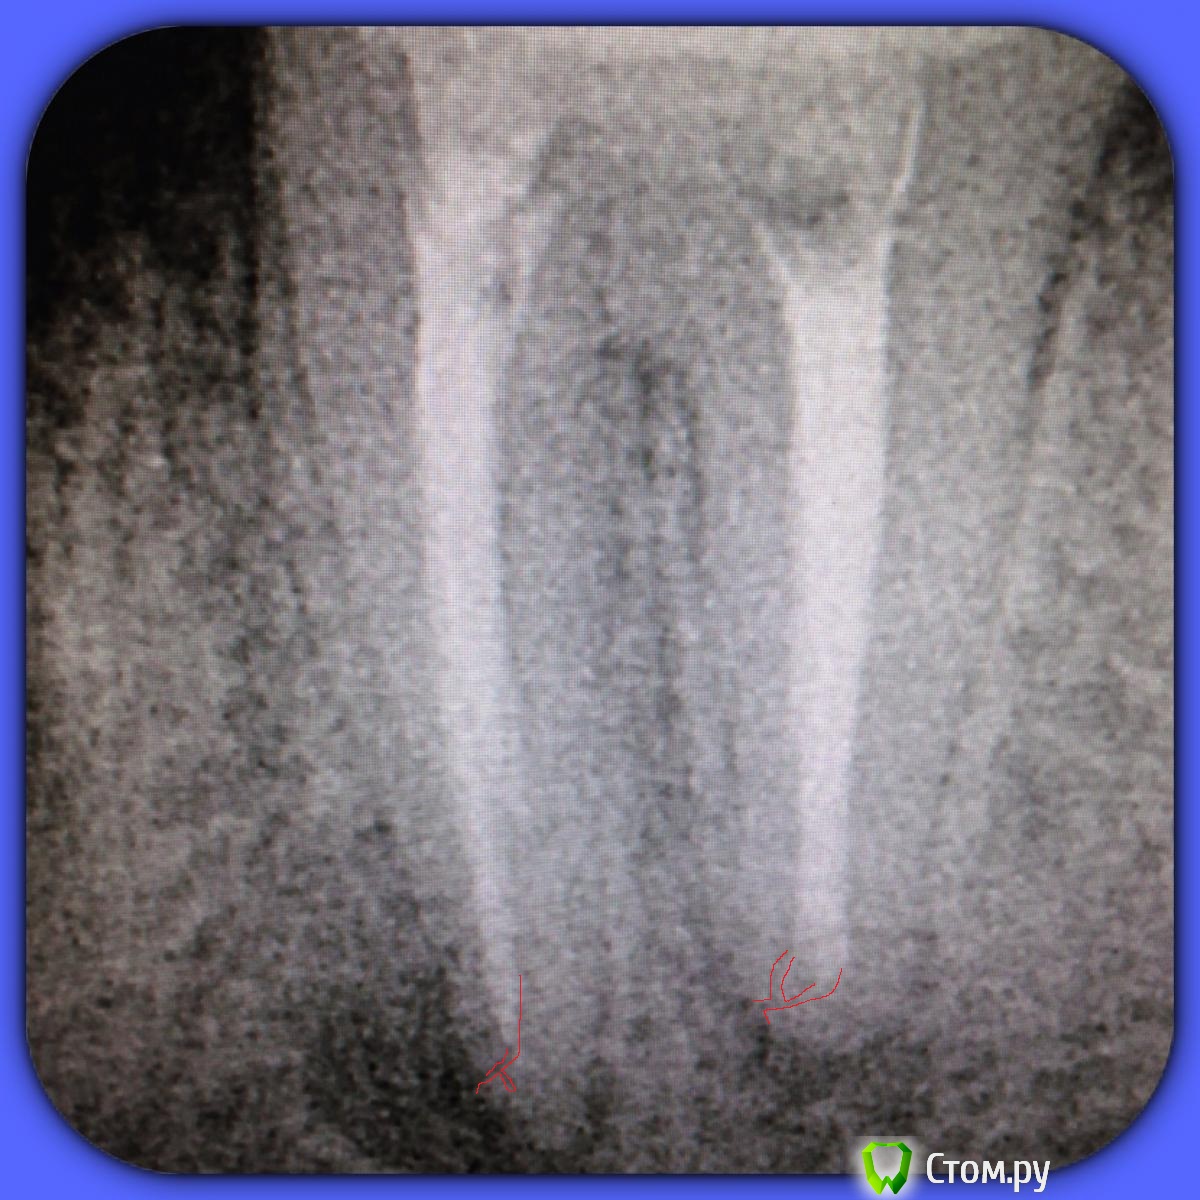

SSTi Опубликовано 13 июня, 2014 Автор Поделиться Опубликовано 13 июня, 2014 37. Медиальная стенка разрушена. Огромная старая пломба. Из жалоб только иногда болезненность по переходной. Редко. Очень. Делаю снимок. Коффер, преп, в дистальном какая-то паста плотная очень, светло-молочного цвета. В медиальный язычный без проблем попал. Щечный пришлось ковырять. Теперь о неприятном. Дистальный распломбировал, прошел, при этом раскрутил 3 протейпера и 1 профайл. В язычном медиальном проблем не было. А вот щечный- жутко узкий, прошел до куда смог. Раскрутил 3 протейпера, 2 профайла, 1 pathfile.... Дальше никак. До апекса еще миллиметров 5 точно. Хорошо хоть без поломок. Ручные к файлы гнулись только так. Даже десятка не идет. В общем очень хорошо помыл и кальций. Не знаю , что с щечным делать??? Биться дальше?? Сомневаюсь, что смогу. Это в процессе. Вот до куда дошел в щечном. С дистального потом убрал со стенок остатки материала Ссылка на комментарий

SSTi Опубликовано 13 июня, 2014 Автор Поделиться Опубликовано 13 июня, 2014 У язычного длина 23.5. В щечный файл заходит на 17-18мм. Надо будет развернуть трубку и сделать под углом в следующий раз. Апекс молчит как партизан в щечном. Ссылка на комментарий